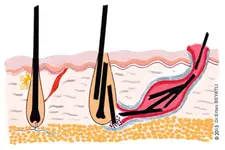

Kuyruk sokumu kıl dönmesi, tıbbi literatürde "pilonidal hastalık" olarak bilinen bir durumdur. Bu hastalık, kuyruk sokumu bölgesinde kılların derinin altına doğru büyüyerek iltihaplanmasına ve enfeksiyon oluşturmasına yol açar. Genellikle genç erkeklerde daha sık görülmekle birlikte, kadınlarda da ortaya çıkabilir. Bu makalede, kuyruk sokumu kıl dönmesinin belirtileri, nedenleri ve tedavi yöntemleri üzerinde durulacaktır. Belirtiler Kuyruk sokumu kıl dönmesinin belirtileri genellikle şu şekildedir:

Bu belirtiler, hastalığın evresine göre değişkenlik gösterebilir. Başlangıçta hafif rahatsızlık hissedilse de zamanla belirtiler şiddetlenecek ve yaşam kalitesini olumsuz etkileyecektir. Nedenleri Kuyruk sokumu kıl dönmesinin kesin nedeni henüz tam olarak anlaşılamamıştır. Ancak, bazı faktörlerin hastalığın gelişiminde etkili olduğu düşünülmektedir:

Bu faktörlerin yanı sıra, hijyen eksikliği ve cilt yaralanmaları da hastalığın gelişiminde rol oynayabilir. Tedavi Yöntemleri Kuyruk sokumu kıl dönmesinin tedavisi, hastalığın evresine ve belirtilerin şiddetine göre değişir. Tedavi seçenekleri genel olarak şu şekildedir: